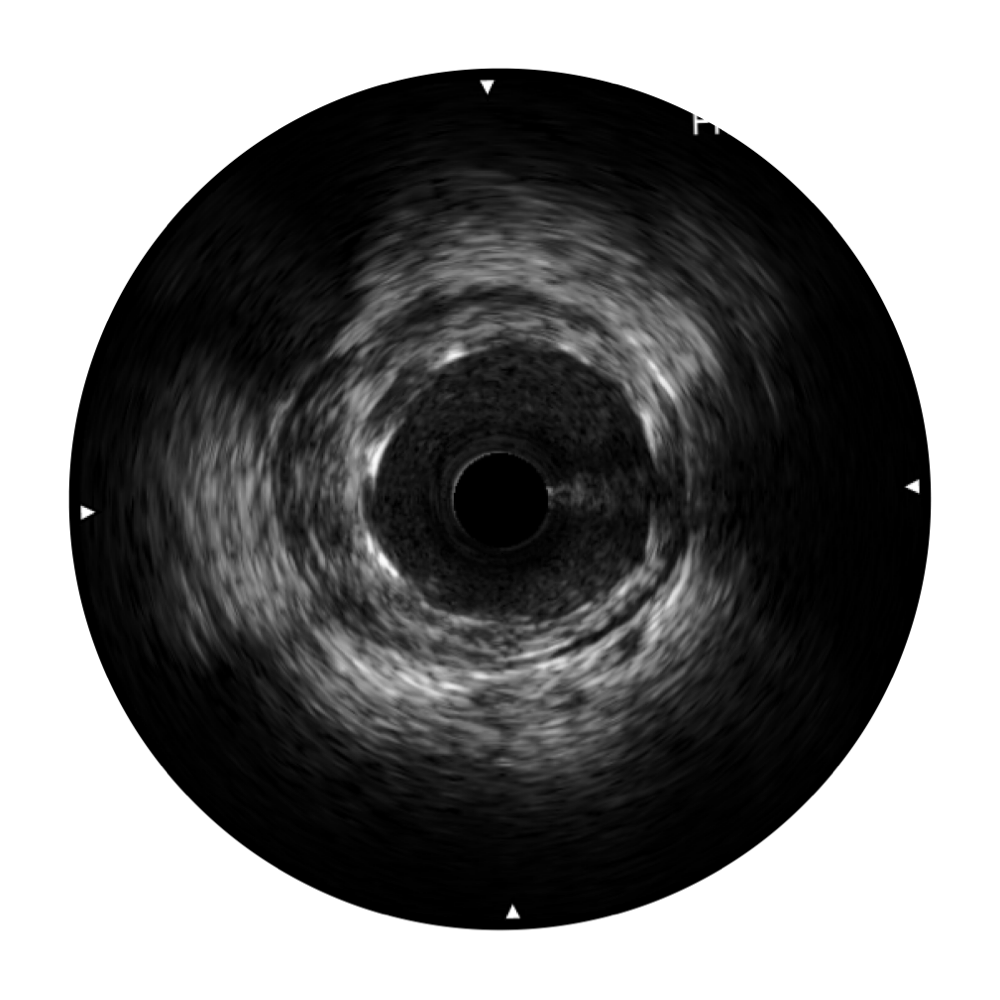

新葡的京集团8814检测站宽频IVUS图像

对比传统IVUS导管成像,新葡的京集团8814检测站宽频IVUS图像的近场支架梁显影更细腻,远场中膜外血管仍清晰可辨,兼顾远中近,兼顾分辨力与穿透深度